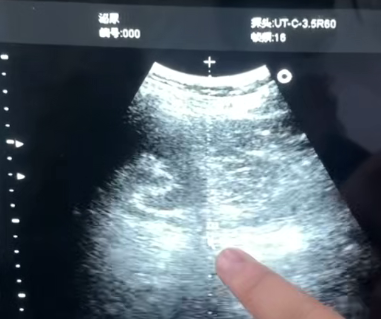

(长沙南湖医院结石中心——体外磁波碎石画面)

在体外碎石治疗前,专家会为患者进行全面的检查,包括泌尿系CT、B超等,精准判断结石的大小、数量、位置、成分,结合患者的年龄、身体状况等因素,量身定制个性化的治疗方案,避免盲目碎石。治疗过程中,专家亲自操作设备,全程把控治疗细节,确保碎石安全、有效;术后,专家会为患者提供专业的康复指导,包括饮食调理、饮水建议、运动指导等,帮助患者快速恢复,降低结石复发率。